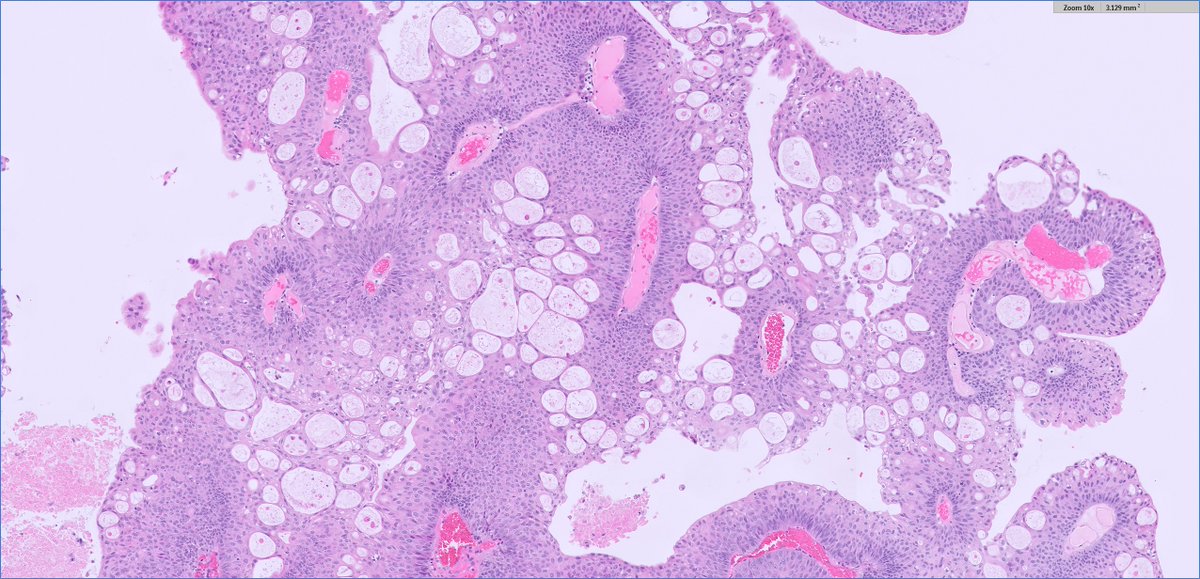

#GUpath TURBT: non-inv papillary urothelial carcinoma (PUC) with admixed microcysts I don't consider this "glandular differentiation" -- I hold out for true apical cytoplasm/cribriform/villoglandular forms/lumina to call pTa PUC w/glandular diff